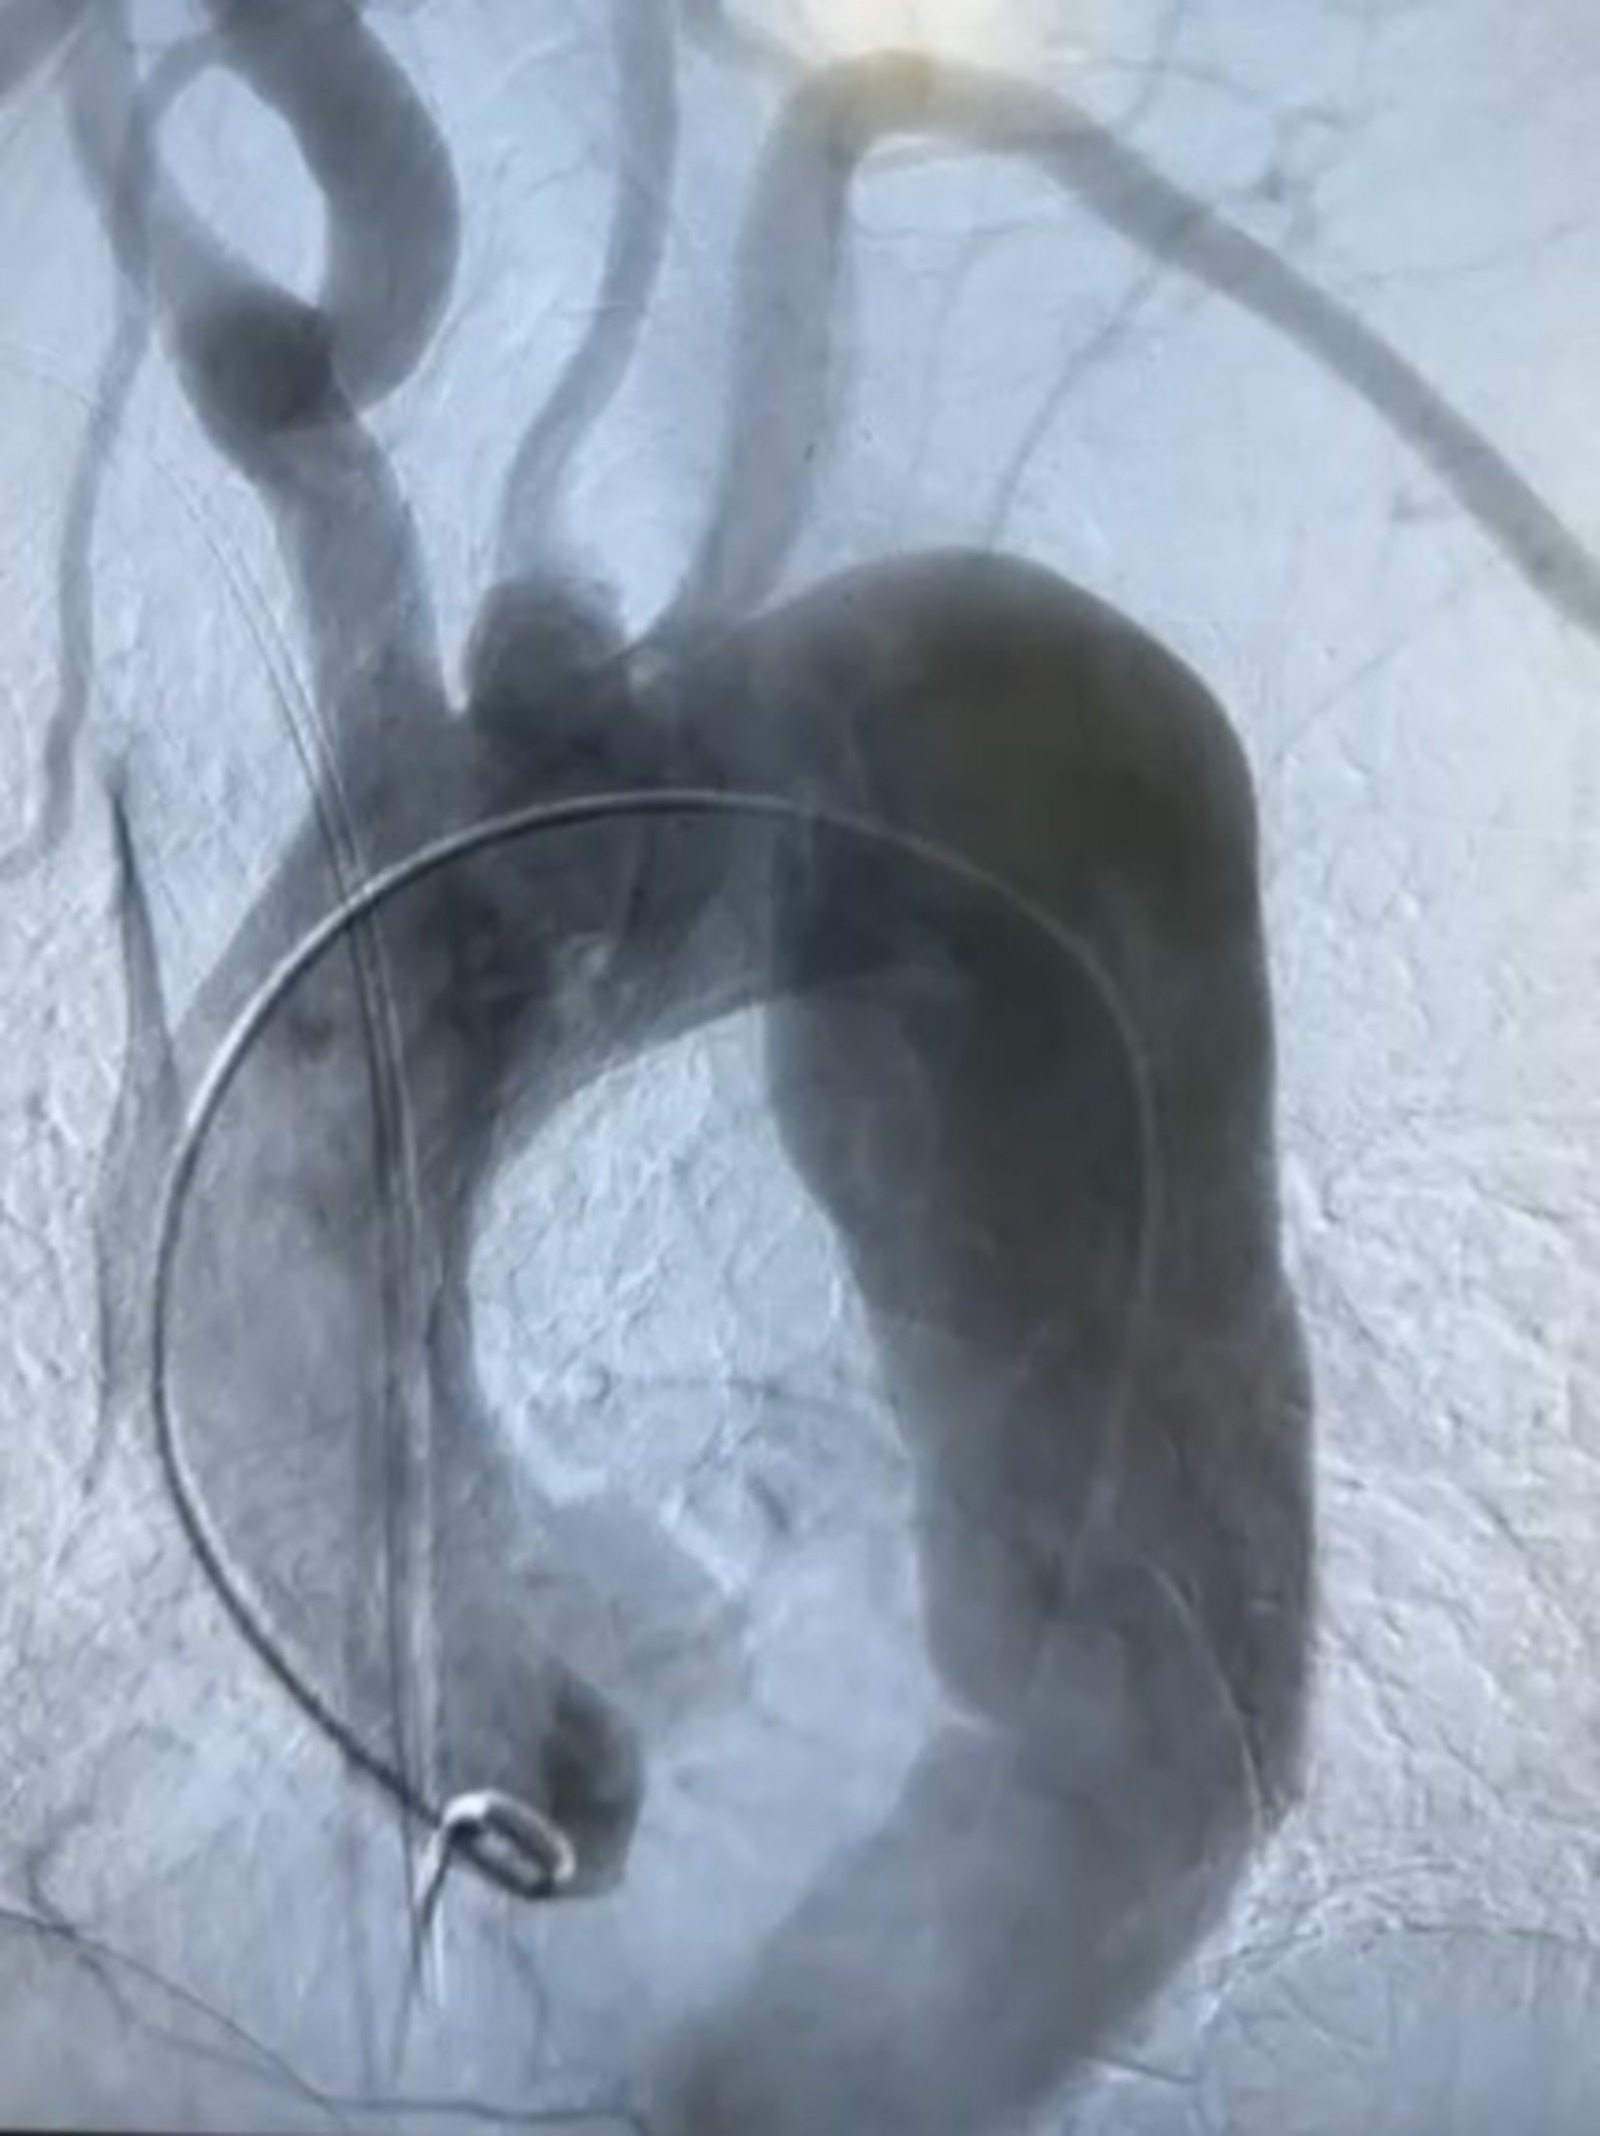

Во время операции на контрольной ангиографии наблюдалось полное восстановление просвета аорты. В составе операционной бригады под руководством заведующего отделением Хафизова участвовали рентгенхирурги Идрисов, Катаев, анестезиолог Челотканов, операционная медсестра Хайдарова.